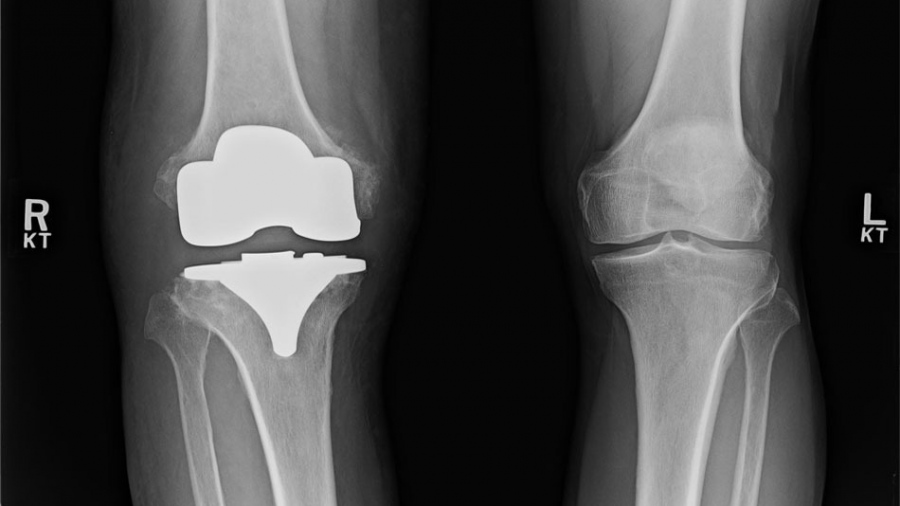

Αρθροπλαστική γόνατος: Ποια αθλήματα επιτρέπονται και μετά από πόσο χρονικό διάστημα είναι ασφαλής η επιστροφή;

Η ολική αρθροπλαστική γόνατος αποτελεί τη μοναδική οριστική θεραπεία της οστεοαρθρίτιδας τελικού σταδίου. Τα τελευταία χρόνια και σε σχέση με ασθενείς που κληθήκαμε να χειρουργήσουμε στο παρελθόν, οι ασθενείς που υποβάλλονται σε αρθροπλαστική γόνατος είναι πλέον νεότεροι, ή αν είναι ηλικιωμένοι, είναι αρκετά δραστήριοι. Υπάρχουν πολλοί παράγοντες που συντελούν στο γεγονός ότι νεότερες ηλικίες αποφασίζουν να προχωρήσουν σε αρθροπλαστική γόνατος. Αρχικά, τα υψηλά ποσοστά παχυσαρκίας, μια από τις αιτίες καταστροφής του χόνδρου. Επίσης, η ένταξη της συστηματικής άσκησης στη ζωή του πληθυσμού, η οποία ναι μεν προάγει την καλή υγεία, αλλά παράλληλα αυξάνει τον κίνδυνο για μετατραυματικές αρθρίτιδες. Τέλος, τα καλά αποτελέσματα του χειρουργείου, τα οποία ενθαρρύνουν όλο και περισσότερους ασθενείς να αναζητήσουν από νωρίς τη λύση για τις ενοχλήσεις που αντιμετωπίζουν στο γόνατο. Με τον τρόπο αυτό, έχουν τη δυνατότητα να επιστρέφουν όσο το δυνατόν νωρίτερα στις δραστηριότητες τους, να μην αντιμετωπίζουν πλέον δυσκολία και πόνο, να μπορούν να συμμετέχουν σε αθλήματα, να  συνεχίζουν να μεγαλώνουν χωρίς λειτουργικά προβλήματα και να κατακτούν καθημερινά τους στόχους που θέτουν, διατηρώντας και τονώνοντας την αυτοπεποίθησή τους.